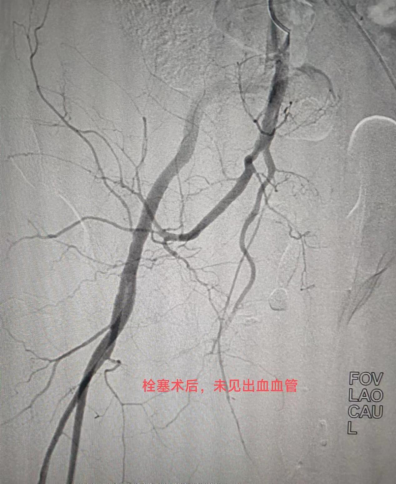

2個(gè)小時(shí)后

栓塞了多處出血的血管

通過(guò)再次造影顯示

完美止血

(圖:栓塞后造影復(fù)查,動(dòng)脈出血消失)